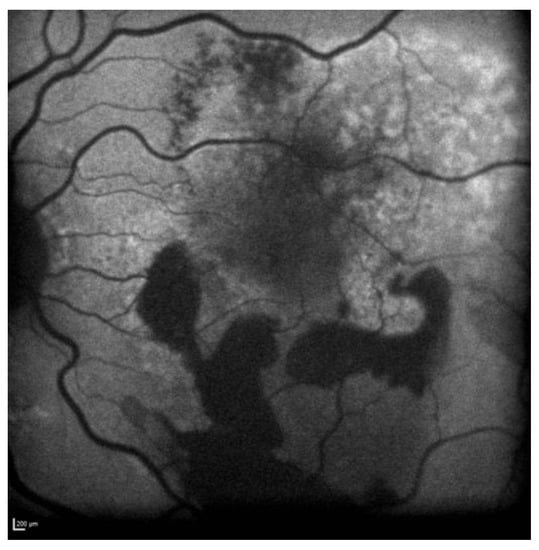

Fundus examination showed right macular drusen and a left macular yellowish elevated lesion with massive retinal haemorrhage.

FAF revealed a hypoautofluorescent macular lesion in the left eye (Figure 8).

Figure 8.

Case 6. Heidelberg Spectralis blue autofluorescence shows a left eye macular hypoautofluorescent lesion.

The OCT scan showed a dry macula with drusen in the right eye and a type 1 MNV with PEDs, intraretinal and subretinal fluid, subretinal haemorrhage, and a haemorrhagic BALAD in the left eye (Figure 9A).

Figure 9.

Case 6. (A) Heidelberg Spectralis optical coherence tomography shows a type 1 MNV with fibrovascular pigment epithelial detachment, subretinal and intraretinal fluid, and haemorrhagic BALAD in the left eye. (B,C) Heidelberg Spectralis optical coherence tomography shows a good response after a year and two years of intravitreal anti-VEGF treatment, respectively.

The OCTA scan confirmed the presence of the left MNV.

A T&E regimen with anti-VEGF intravitreal injection therapy was commenced. The patient showed an initial good response to the treatment (Figure 9B). Unfortunately, over the following years, the worsening of the condition was observed despite treatment. Thus, the patient switched to a different anti-VEGF molecule.

To date, the patient is still on treatment. The left BCVA was 0.4 logMAR when last examined. The last OCT scan showed intraretinal fluid and an improved BALAD (Figure 9C).

Figure 10 shows Optos Ultra-widefield colour and autofluorescence imaging of the left eye macular lesion two years after the start of the treatment.

Figure 10.

Case 6. Optos Ultra-widefield colour and autofluorescence imaging of the left eye after two years of intravitreal anti-VEGF treatment, showing a yellowish (A) and hypofluorescent (B) macular lesion. The retinal haemorrhage was fully resolved (A,B).